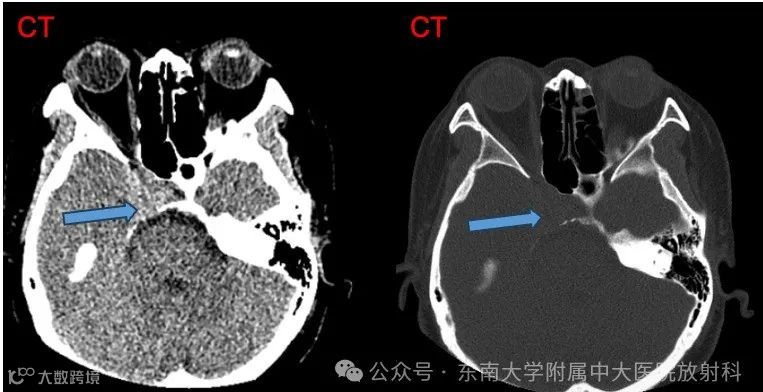

女,42岁 主诉:检查发现鞍区占位4天

现病史:患者4天前因“多关节疼痛”至我院风湿科就诊,考虑纤维肌痛,排查颅脑 MR 时发现鞍区占位。患者自觉鼻根至前额发胀,偶有头晕,按感冒及鼻炎处理无明显效果。无发热寒战,无视力障碍,无言语功能障碍,无心慌胸闷,无腹痛腹胀。现患者为求进一步诊治至我院就诊,病程中,患者神志清,精神可,饮食可,睡眠一般,二便正常,近期体重无明显下降。实验室检查无特殊

影像学表现